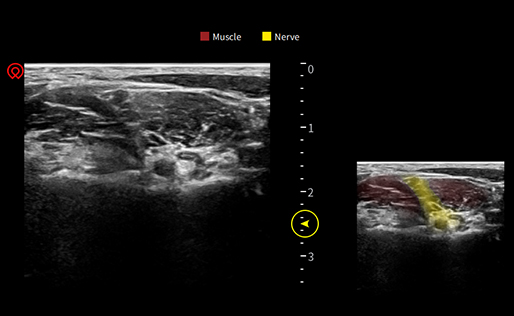

wiNeedle - Tecnología

Inteligente de Mejora de Agujas

Dirección automática del haz

Detección inteligente de la punta y el eje de la aguja

Excellent Clinical Images

Application pictures